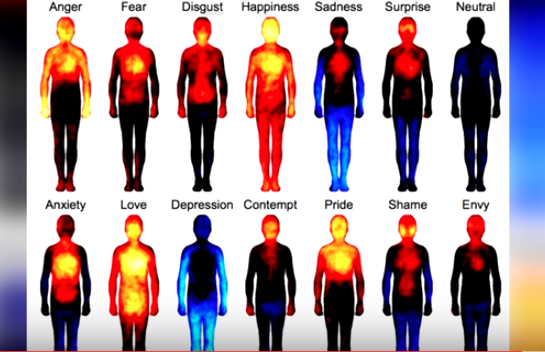

15 cose che non sai sul tuo corpo

Giocare all’Allegro Chirurgo può far sembrare semplice il funzionamento del corpo umano, ma probabilmente ci sono cose che nessuno di voi sa sul proprio organismo.

Ecco la classifica delle 15 curiosità più strane sul nostro corpo.